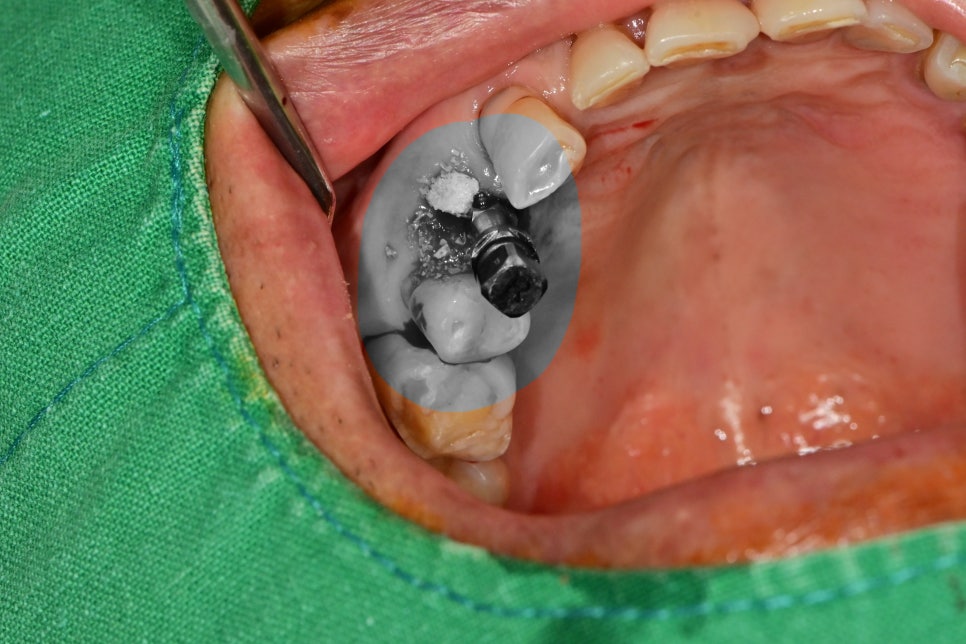

발치 및 임플란트 수술

예상한 것처럼 한쪽 뿌리가 부러져있었습니다.

분리된 뿌리까지 완전하게 발치를 한 후 발치 부위의 염증조직을 깨끗하게 제거를 한 후

CT 분석을 토대로 수술 방향을 잡았습니다.

사진에 보듯이 수술과 동시에 볼륨 유지를 위해 치조골이식술을 진행한 사진입니다.

술후 사진을 보면 수술 전 CT를 찍는 것이 얼마나 도움이 되는지 알 수 있는 사진입니다.

임플란트 초기 고정이 좋았지만 주변에 없는 뼈에 시행한

치조골이식술이 골화가 제대로 이루어질 때까지

자극을 주지 않고 충분히 기다린다면 좋은 결과가 나올 것 같습니다.